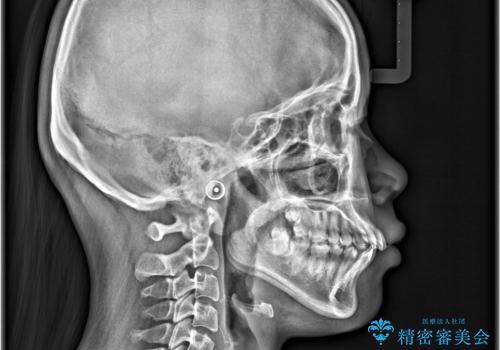

- 「歯のでこぼこと捻じれを治したい」を主訴に来院された患者様です。矯正検査の結果、上顎前歯がかなり唇側傾斜という結果になったので上下左右4番を抜歯をしワイヤー矯正で治療を行いました。

抜歯矯正でしたが順調に治療が進み2年で矯正治療を終えることが出来ました。歯のでこぼこや捻じれが治り、口元も下がって患者さんも大変満足されていました。